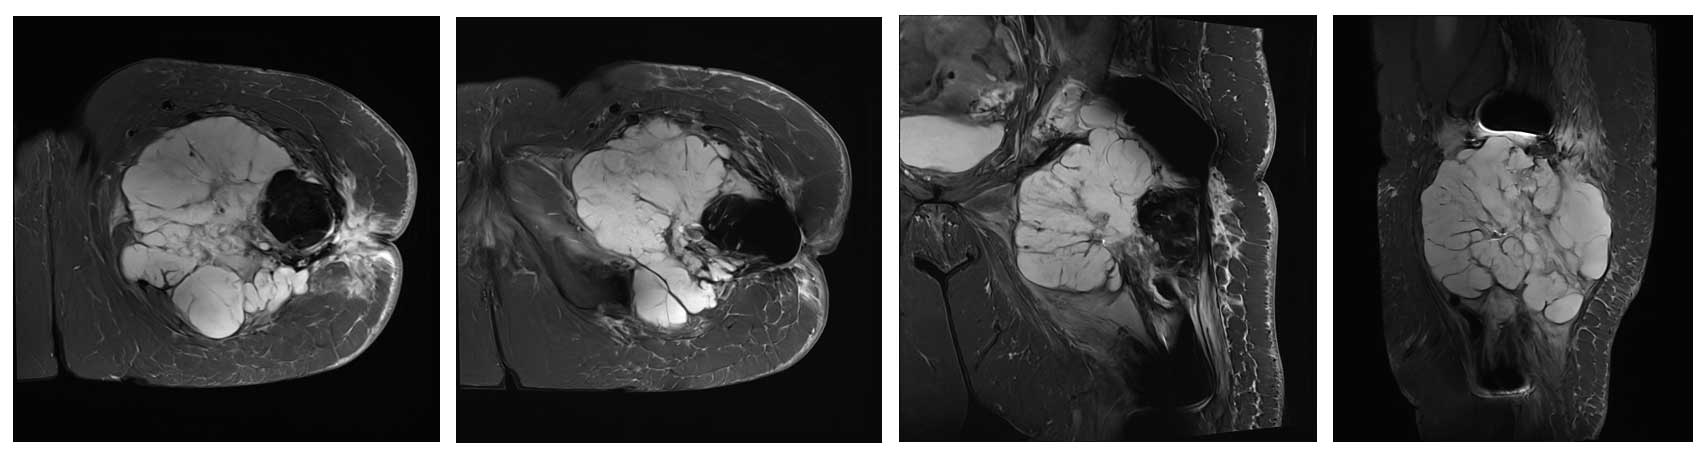

Ameliyat Öncesi: MR’da kalça eklemine uzanım gösteren büyük yumuşak doku kitlesinin eşlik ettiği düzensiz sınırlı büyük tümör dokusu görülmekte.